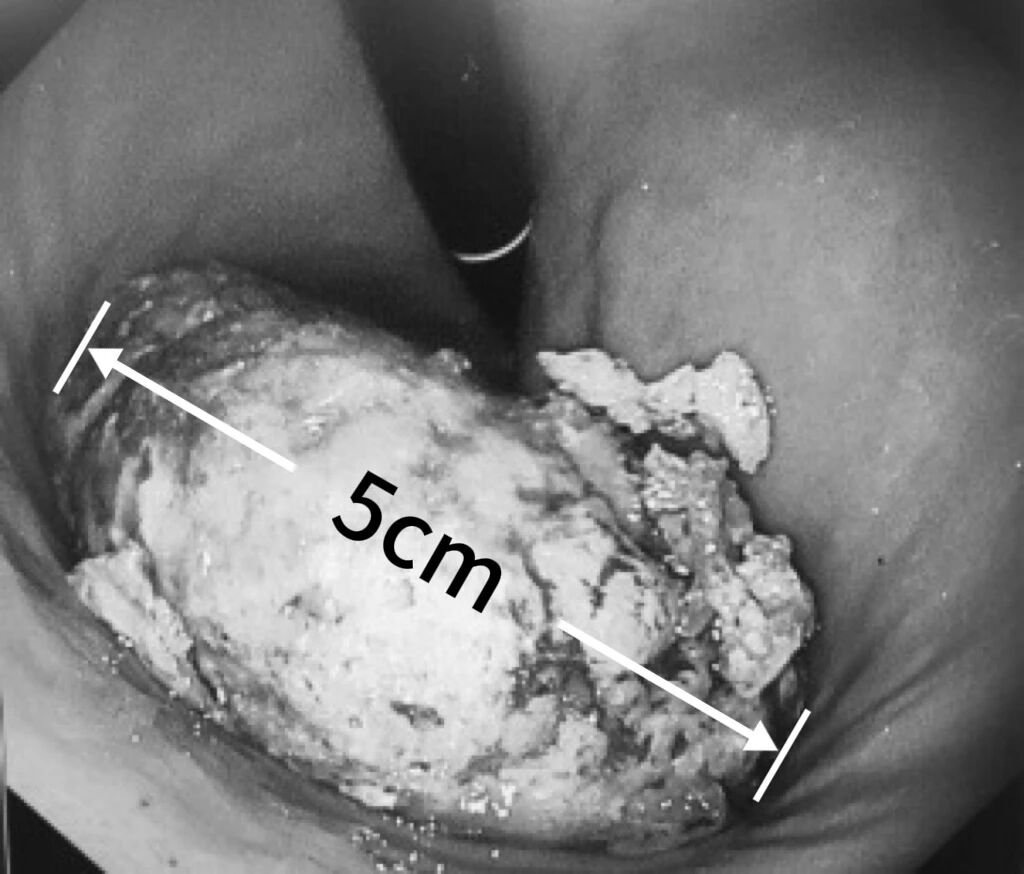

大量吃山楂竟致胃内长5cm结石!玉溪市中山医院内镜下碎石术巧解难题

2025年12月11日,58岁患者刘阿姨因腹痛、恶心、呕吐等不适症状至玉溪市中山医院消化内科就诊。经胃镜检查,医生竟在她的胃里发现一个直径达5cm的胃结石!通过详细问诊,医生了解到刘阿姨近期曾大量食用山楂。据消化内科主任肖静介绍,胃结石的形成多与食用富含鞣酸的食物相关,柿子、山楂、黑枣等都是常见“诱因”。这些食物中的鞣酸在胃内与胃酸、蛋白质相遇后,会发生化学反应形成不溶性沉淀物,长期聚集便会凝结成坚硬的结石...